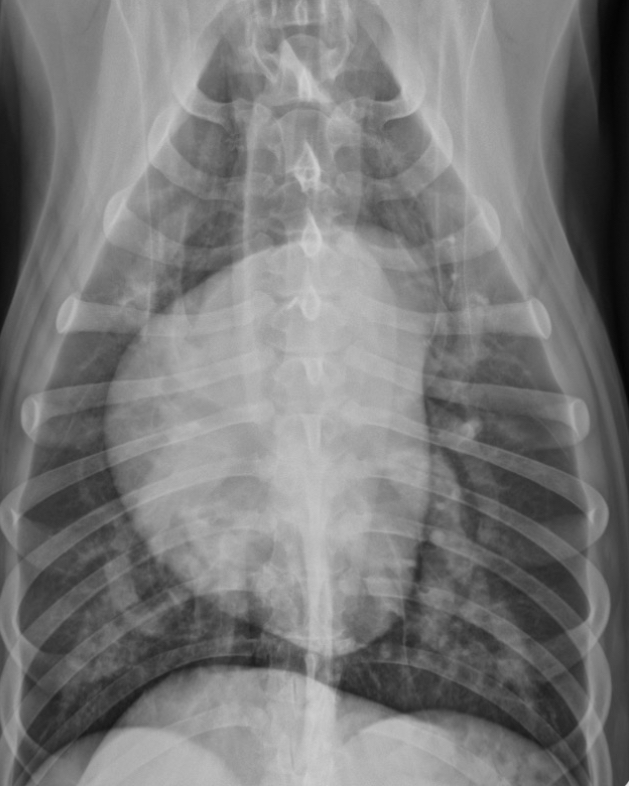

Features of generalized cardiomegaly in dogs and what disease is associated with this?

-combo roentgen signs involving L and R cardiac chambers

-dogs often get mitral dz which results in both L+R heart enlargement

-tall + wide, sternal contact

what part of the heart is enlarged in this dog

Generalized (whole thing)